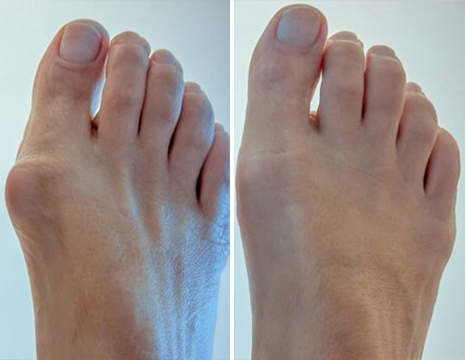

Dr. Milan Kokavec: Hlavnými komplikáciami kĺbových patológií sú zmeny

tvaru kĺbov, vážne obmedzenie pohybu a ankylóza, ktorá kĺb úplne znehybní a fixuje ho v

polohe, ktorá je často nesprávna.

Ak kĺby nie sú úplne ohnuté a natiahnuté, dochádza k

narušeniu osí končatín, pozdĺž ktorých sa rozkladá hlavné mechanické zaťaženie tela. V

dôsledku systematického porušovania správnej osi končatín sa zvyšuje zaťaženie ostatných

kĺbov, čo vedie k sekundárnym degeneratívnym zmenám.

To je dôležité najmä v prípade kĺbov, ktoré

nesú váhu: koleno, bedro, členok.

Človek pociťuje VYHNUTÚ EXTRÉMNU BOLESŤ,

kvalita života pacienta sa znižuje: človek sa nemôže normálne pohybovať, vykonávať každodenné

domáce práce; je nútený zmeniť zamestnanie, vzdať sa koníčkov a v 80 % prípadov sa stáva

invalidom.